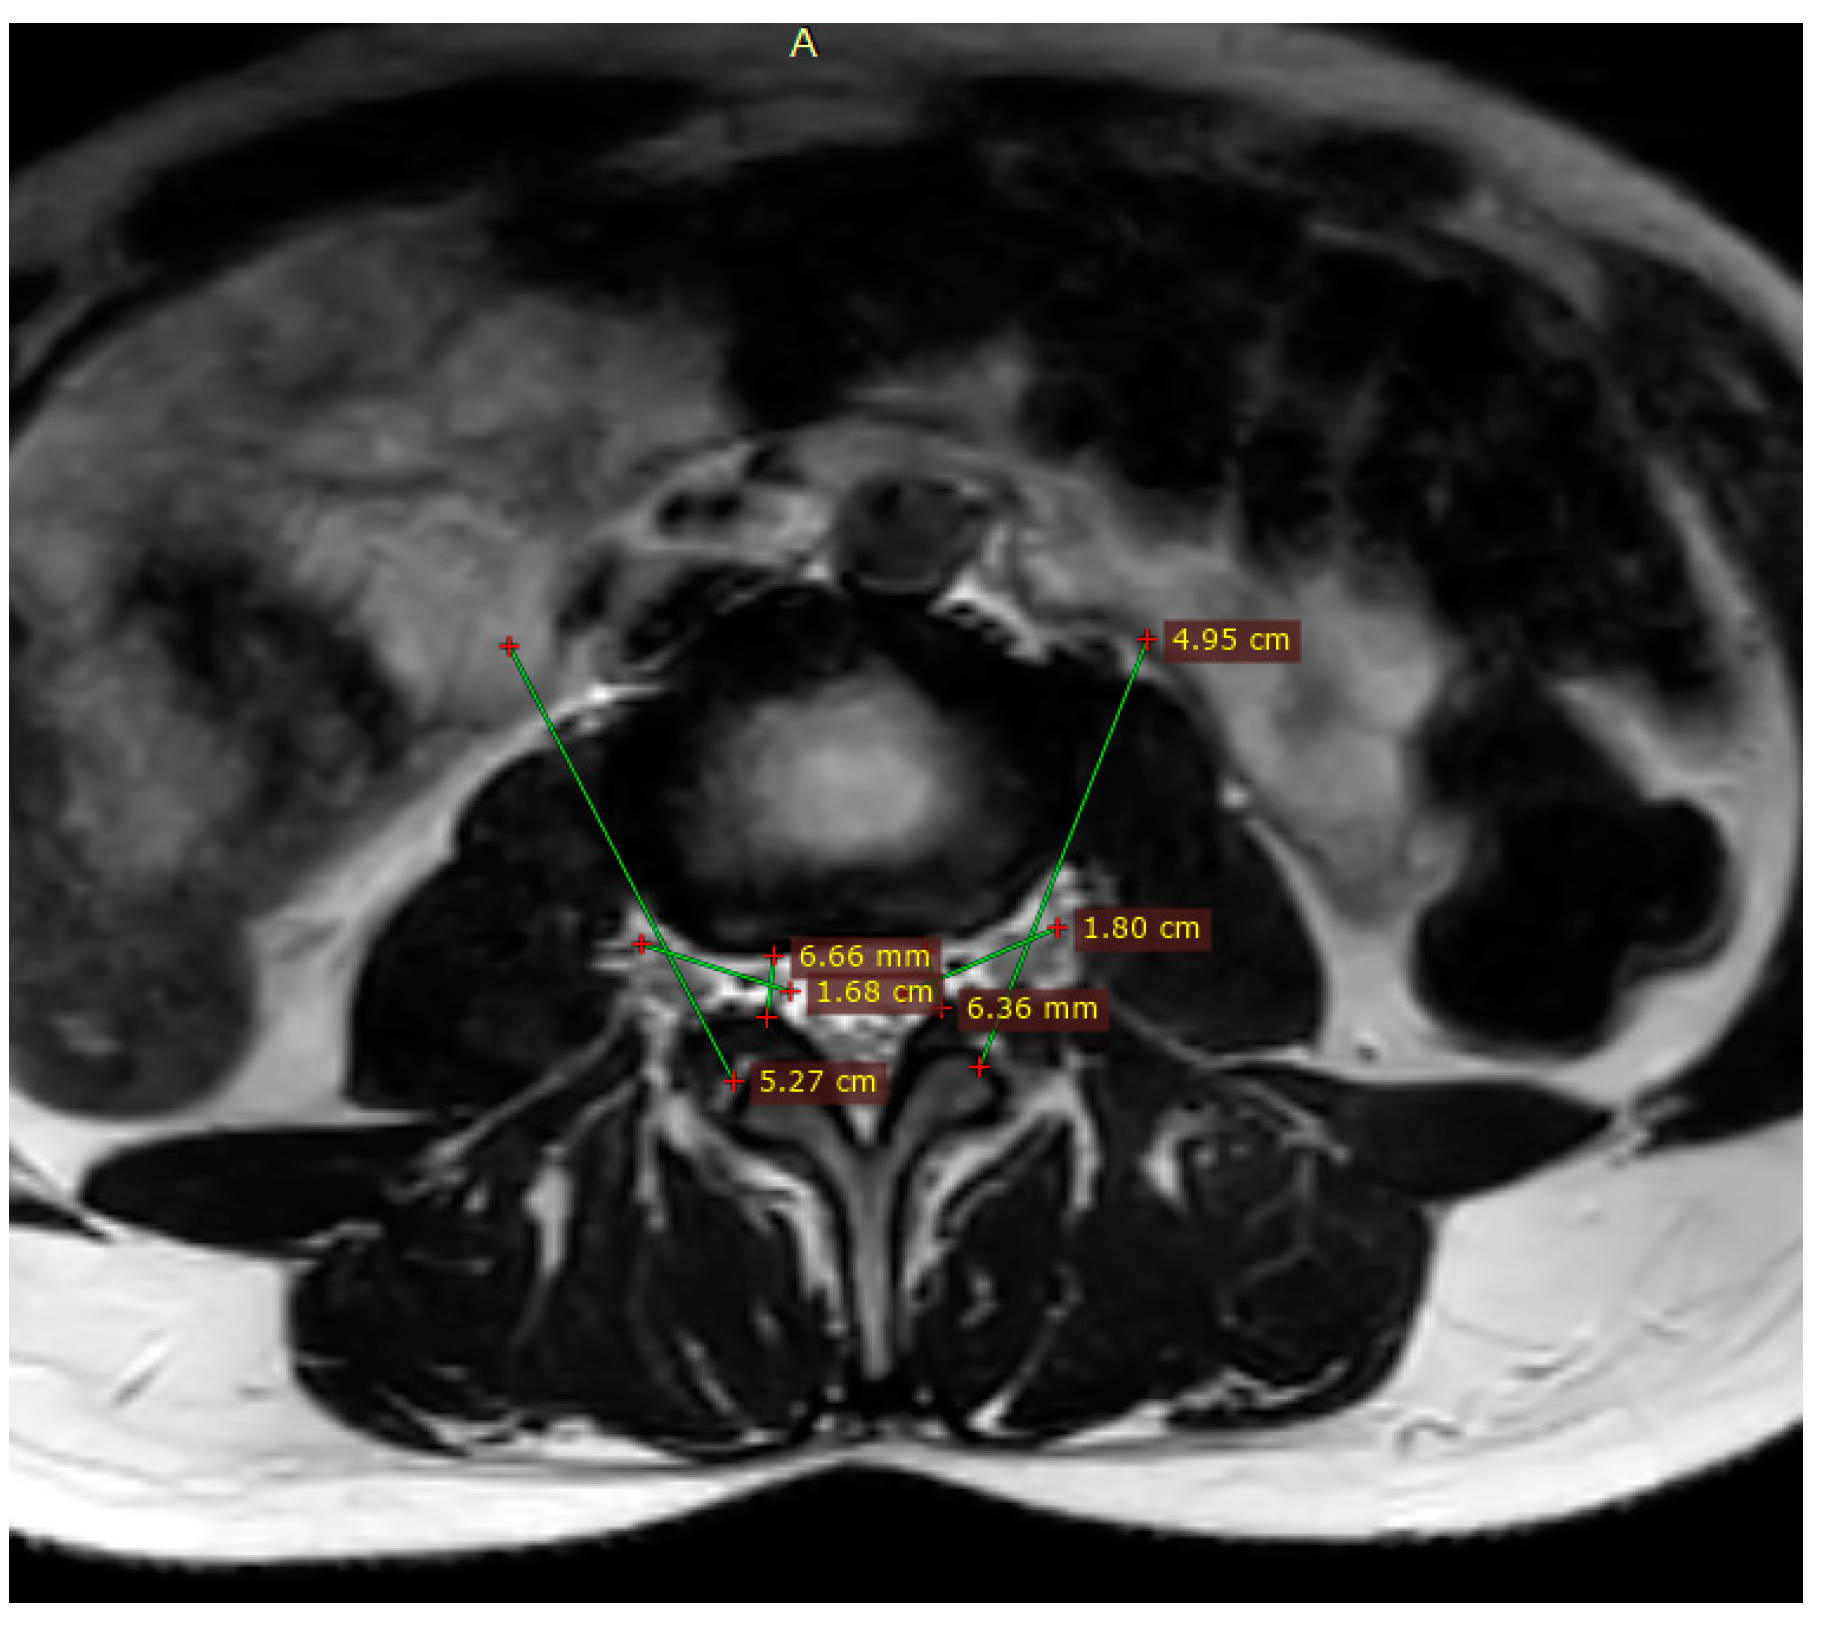

Magnetic Resonance Imaging (MRI)

2.7.1. Volumetric Analysis

3.1. Volumetric Analysis of Lumbar Foramina